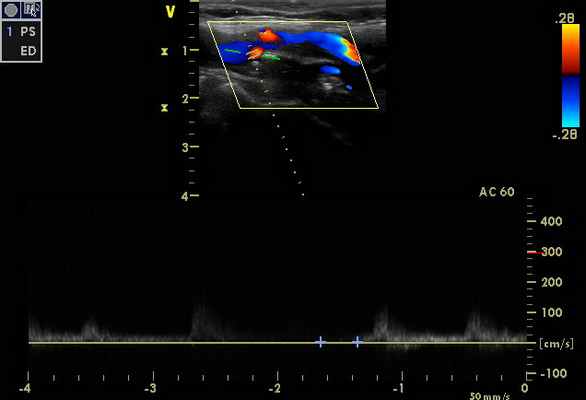

При проведении дуплексного сканирования экстра- и интракраниальных сосудов определяются эхографические признаки стенозирования до 90-95% по НСА справа и субокклюзии-окклюзии ВСА справа (рис. 1, 2)

Признаки стенозов в V 2 сегментах позвоночных артерий с обеих сторон - по спектральным характеристикам - 75-85%, (правая ПА - на рис. 3). На рис. 4 – признаки субокклюзии – окклюзии ОСА слева (состояние после стентирования и эндартерэктомии - 2011 г.).